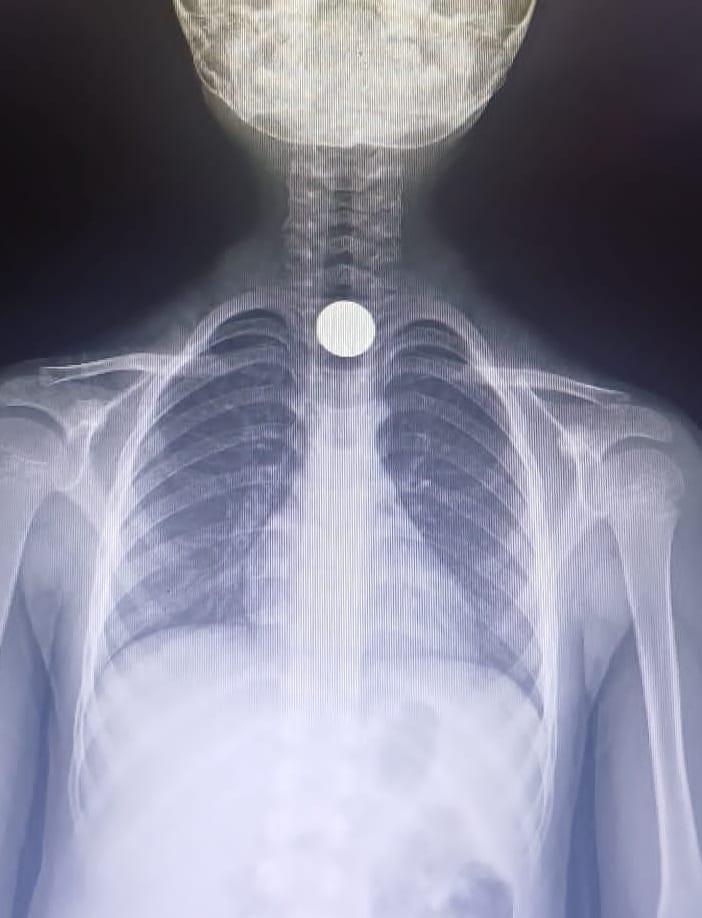

Yavuz YILMAZ/İNEGÖL (Bursa), (DHA)-BURSA'nın İnegöl ilçesinde Yusuf Z.'nin (5) yemek borusuna takılan madeni para, operasyonla çıkartıldı.

Olay, saat 14.00 sıralarında İnegöl ilçesi Mesudiye Mahallesi'nde meydana geldi. Sarmaşık Sokak'taki evlerinde oynayan Yusuf Z., fenalaşınca ailesi tarafından özel otomobille İnegöl Devlet Hastanesi'ne götürüldü. Tetkiklerde, yemek borusuna 50 kuruşluk madeni para kaçtığı tespit edilen Yusuf Z., ambulansla Bursa Yüksek İhtisas Eğitim ve Araştırma Hastanesi'ne sevk edildi. Yusuf Z.'nin yemek borusundaki para, burada yapılan başarılı ameliyatla çıkartıldı. (DHA)